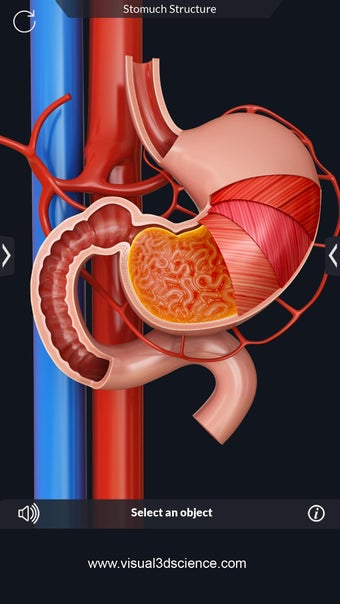

La anatomía humana es una aplicación educativa médica que te permite explorar el cuerpo humano desde todos los ángulos. Ofrece una mirada detallada a la anatomía de los diferentes sistemas, así como a los órganos y sus funciones. Es una referencia perfecta para estudiantes y profesores de medicina.

Puedes seleccionar cada parte del cuerpo por separado para ver su nombre o leer información relacionada. Puedes ocultar y mostrar cada parte del cuerpo, así como rotar 360° alrededor de un modelo 3D altamente realista. Puedes dibujar en la pantalla o compartir capturas de pantalla con tus amigos. Puedes encontrar la definición de cada parte del cuerpo y su anatomía.